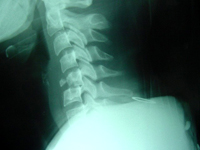

Las lesiones de la columna vertebral pueden clasificarse en tres tipos:

- El tipo de lesión más frecuente y menos grave es la fractura-acuñamiento. Se caracteriza porque el cuerpo vertebral, habitualmente cuadrado, adquiere la forma de una cuña en su región anterior. Muy raramente se asocia a una lesión neurológica.

- El segundo tipo en frecuencia es la fractura-estallido. En esta fractura el cuerpo vertebral "estalla" en múltiples fragmentos. Suele ser debida a traumatismos de alta energía y no es infrecuente que se asocie a lesiones neurológicas ya que los fragmentos óseos pueden desplazarse al interior del canal raquídeo y comprimir las estructuras nerviosas. No obstante, la presencia de estos fragmentos dentro del canal no implica necesariamente que se haya producido o vaya a producirse una lesión neurológica.

Por último, la forma más grave de lesión vertebral es la fractura-luxación. A consecuencia de traumatismos de muy alta energía, se rompen los ligamentos que unen a las vértebras entre sí, y dos vértebras contiguas pierden su relación. Esta pérdida de posición distorsiona también la forma del canal medular y, por dicha razón, en muchas de estas lesiones se produce una lesión de la médula espinal.